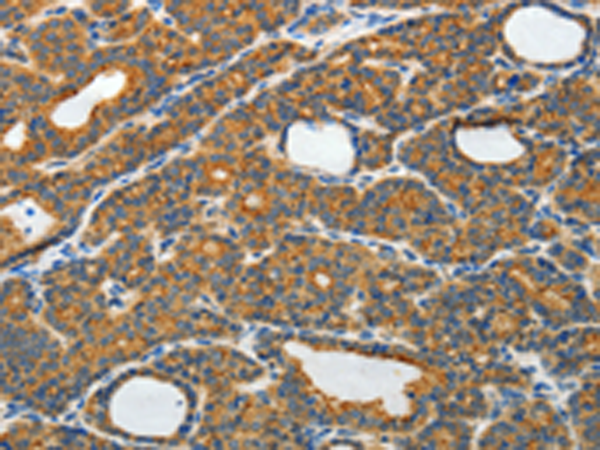

分类: 科研抗体货号: P07551别名: PBP; HCNP; PEBP; RKIP; HCNPpp; PEBP-1应用: WB,IHC反应种属: Human, Mouse, Rat